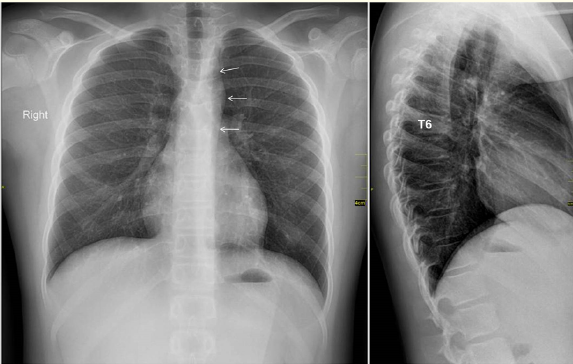

Long-term Course in a Patient with a Broken U-stabilizing Device in the Lumbar Spine

Fumihiko Hara, Masakatsu Saitoh, Masamichi Oh, Ichiro Miyagi, Jin Nakashima, Sei Mihira, Wataru Shimada and Hiraku Kikuchi. 13(11): 20-25.